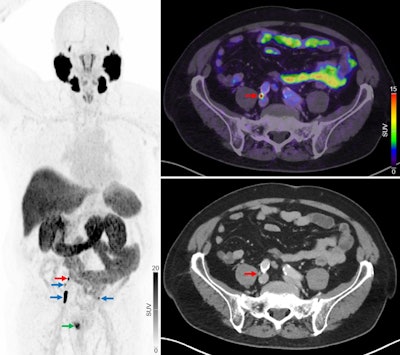

Primary staging of a patient with high-risk prostate cancer. Initial F-18 NaF-PET/CT showed no regional or distant metastases. The patient later underwent radical prostatectomy with extended pelvic lymph-node dissection. In a blinded project review, F-18 PSMA-PET/CT revealed multiple intrapelvic lymph node metastases (blue arrows) and 1 lymph node metastasis near bifurcation of right common iliac artery (red arrows). Primary prostate lesion is also visible (green arrow). Three months postoperatively, the patient’s PSA remained elevated (0.67 ng/mL), and bicalutamide therapy was started.Journal of Nuclear Medicine